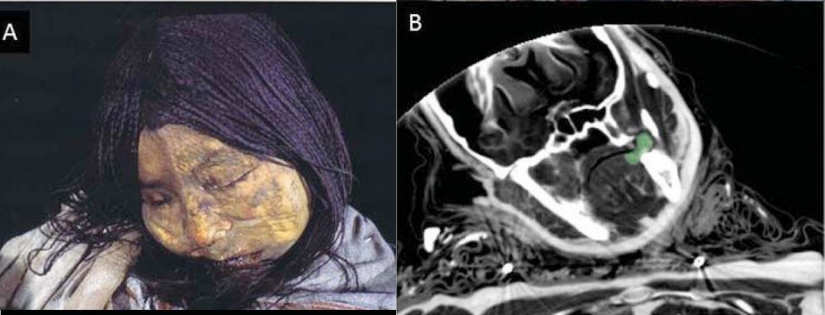

11. No hace mucho tiempo que se dio a conocer que la misteriosa momia es más que un siglo antes en la colección del Museo alemán, puede ser una mujer de la tribu de los Incas, que murió a causa de múltiples golpes en la cabeza, probablemente durante el asesinato ritual.

12. A la cabeza de la momia fueron goma de Alpacas y llamas. Se podría decir que la momia es nativa de América del Sur.

13. Su cráneo fue también característico de la "variedad" de los huesos que sólo las Naciones de América del Sur, pero no Europeos.

14. Por un lado la cara de la momia parecía bastante normal, pero en el interior de su cráneo, los huesos estaban rotos.

15. Como se puede ver, la parte frontal de su cráneo está completamente fracturado.

16. Las imágenes también mostraron signos de la compactado de la pared del corazón y una inflamación del intestino. Probablemente, esto fue causado por la enfermedad de Chagas.